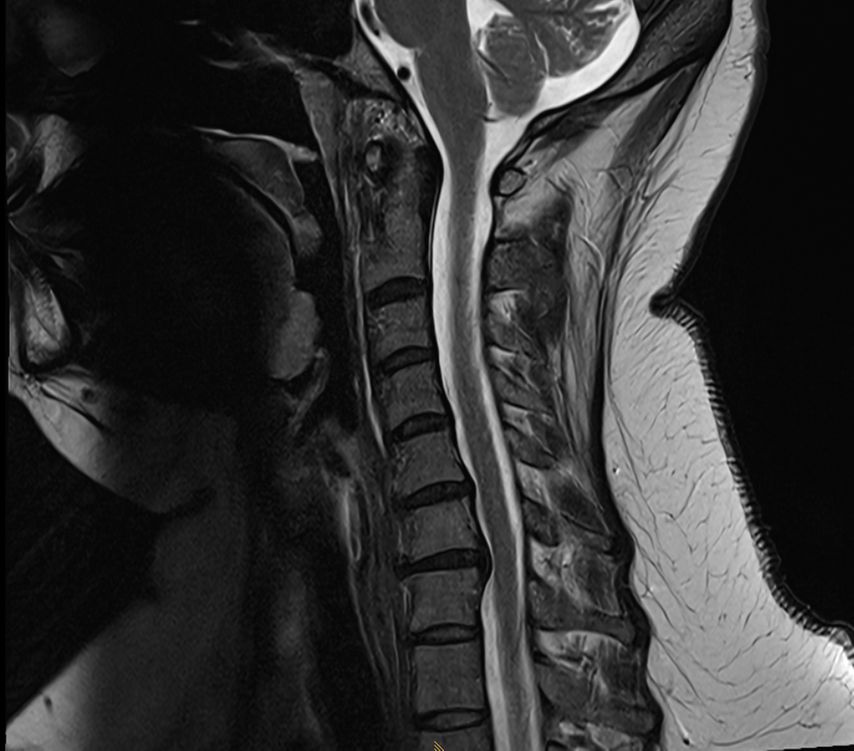

Die Navigation stellt nicht nur beim Einbringen von Implantaten eine Hilfe dar, sondern kann auch in anatomisch herausfordernden Situationen rein zur Verbesserung der Orientierung zu Hilfe genommen werden. Mögliche Anwendungsfelder stellen hier beispielsweise die untere HWS oder der zervikothorakale Übergang dar, welche im konventionellen Röntgen teilweise schwer darstellbar sind. Abbildung 16 zeigt den MR-Befund einer 32-jährigen Patientin, die auswärtig zur ACDF C6/7 indiziert wurde, wobei der Eingriff dort aber aufgrund der Unmöglichkeit, die HWS unter Durchleuchtung entsprechend einzustellen, nicht erfolgte. Abbildung 17 zeigt das intraoperative Röntgen mit bereits kräftigem Schulterzug, in dem aber nur mehr das Segment C4/5 sicher beurteilt werden kann. In diesem Fall erfolgte mittels O-Arm der Eingriff navigiert. Ein anderes Beispiel ist die Anwendung zur Orientierung bei Osteotomien, wo die Navigation an unserer Klinik ebenfalls standardmäßig angewendet wird. Abbildung 18 zeigt einen intraoperativen Screenshot im Rahmen der Navigationsanwendung bei einer thorakalen Corporektomie (Th12) von dorsal im Rahmen einer Tumorresektion. Auch bei verkalkten Bandscheibenvorfällen, wie in Abbildung 19 dargestellt, kann die Navigation zur besseren intraoperativen Orientierung herangezogen werden. Ein weiteres Beispiel der vielfältigen Anwendungsmöglichkeiten der Navigation zeigt Abbildung 20. In diesem Fall wurde im Rahmen einer C1/2-Verschraubung nach Harms das Gelenk C1/2 beidseits navigiert zur besseren Fusion angefrischt.